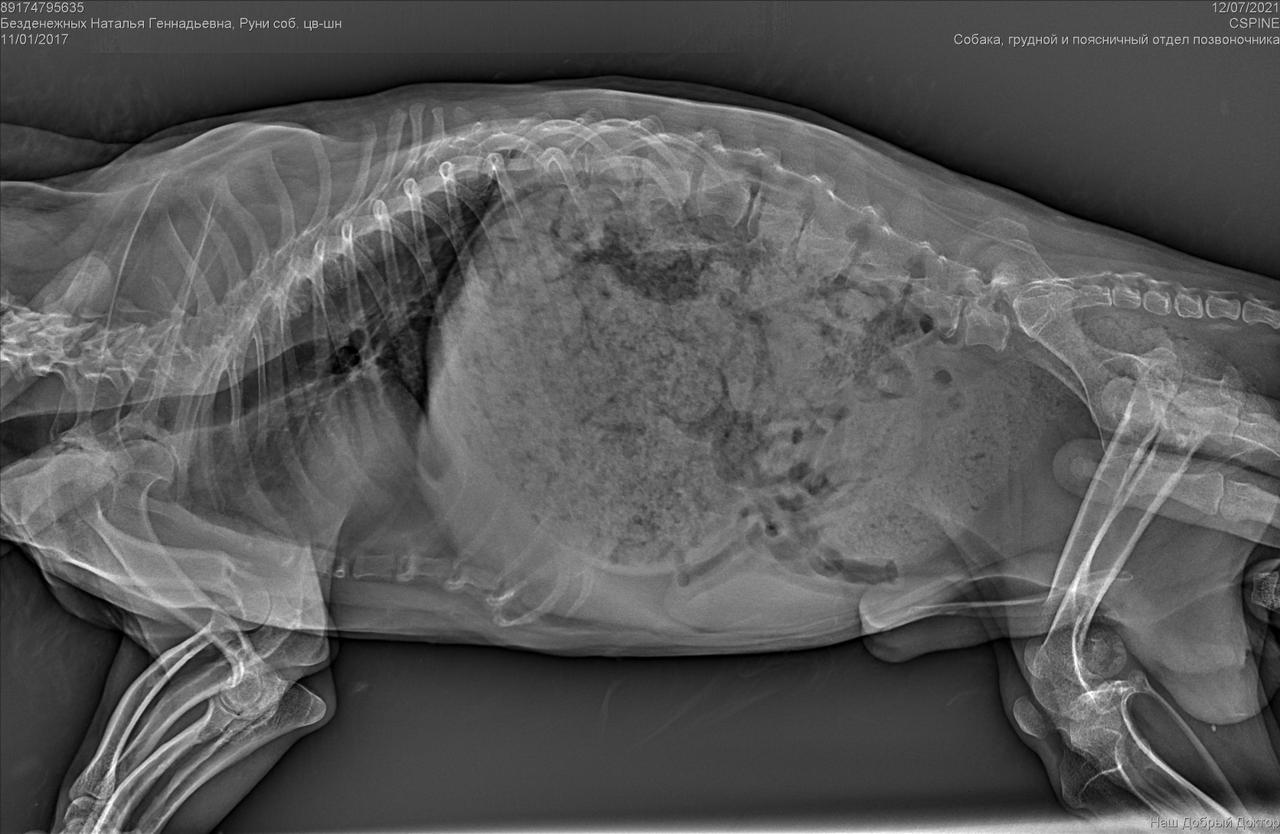

Сегодня утром под окнами дома, по адресу Дмитриева 1, был найден такой замечательный парень, задние лапы похоже перебиты, оставить умирать его я не смогла. Кто-то безжалостно выбросил маленького на улицу и оставил умирать, без еды и питья. Забрала временно к себе, сегодня повезем к ветеринару, оставить у себя возможности нет(моя собака в стрессе) , может кто то его ищет или хочет взять себе, давайте найдём пёсику дом (мама и папу)

С собакой сегодня поедут в клинику. Передержать и полечить смогут. Попросила в клинике посмотреть клеймо и посканировать ип.

ПОнадобится наша помощь с оплатой лечения и поиском дома.